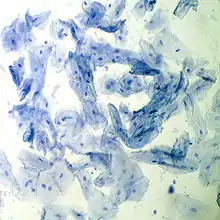

Mucoasa bucală de om văzută la microscop, (coloraţie cu albastru de metilen)

Celulă a mucoasei bucale umane LM (coloraţie cu albastru de metilen)